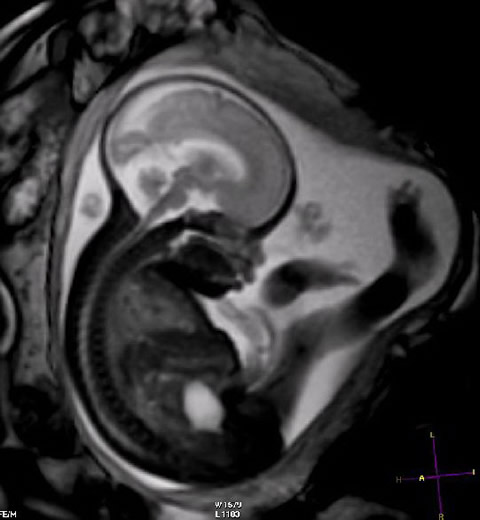

Resonancia magnética: no se detectaron efectos adversos en el primer trimestre del embarazo

Sin embargo, el uso de medios de contraste con gadolinio en cualquier trimestre se asoció con un aumento de complicaciones durante y después del embarazo. JAMA, 6 de septiembre de 2016